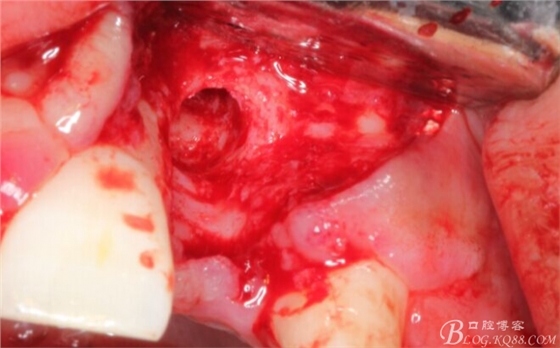

有老師問我,為什么不在此時(shí)同期植骨同期植入植體?我的觀點(diǎn)是:不要一次做太多事情,做得越多風(fēng)險(xiǎn)越高。再說,此時(shí)軟組織不健康,沒有健康的軟組織如何能保證GBR的成功?所以,我僅放了一塊膠原蛋白就縫上了。

事實(shí)證明,我的做法沒有錯(cuò)誤,一個(gè)月后,軟組織健康愈合。鄰牙軟組織沒有退縮。

再次翻瓣。